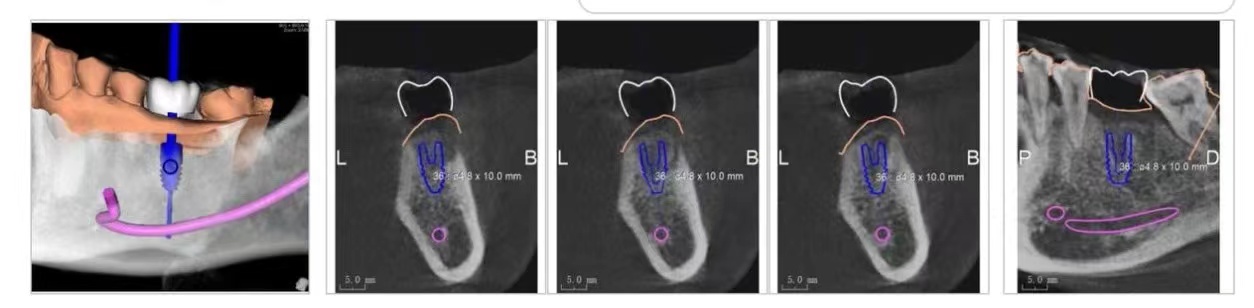

数字化微创种植方案标识出神经、血管、种植体的位置

数字化精准微创种植技术利用德国数字化设备,将患者的牙齿状况生成可视化的数据模板,利用3D打印技术实时制作种植导板,使术中种植体的角度和深度得到精准控制,实现精准微创种植。

在确认了种植方案后,为达到精度在毫米间的种植手术,准确避开患者不利的口内问题,设计并制作3D数字化种植导板是至关重要的一步。这个小小的种植导板,可谓是医生在术中的最强引导工具。

透过数字化导板,医生可以快速准确定位种植位点,种植的角度深度都可以精确到毫米之间,术中不易出血还无需缝合伤口。